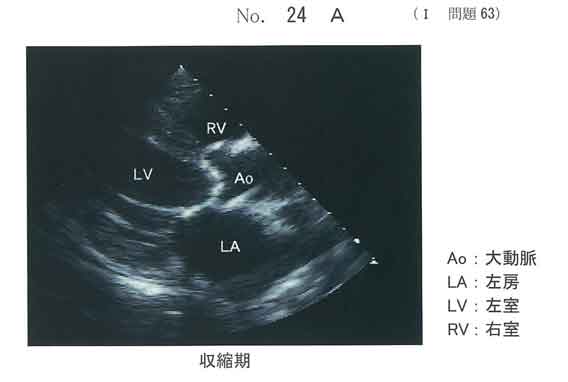

c。(AS)

最高血流速度が4m/秒をこえており、高度の大動脈弁狭窄症。

有症状の高度AS→弁置換術